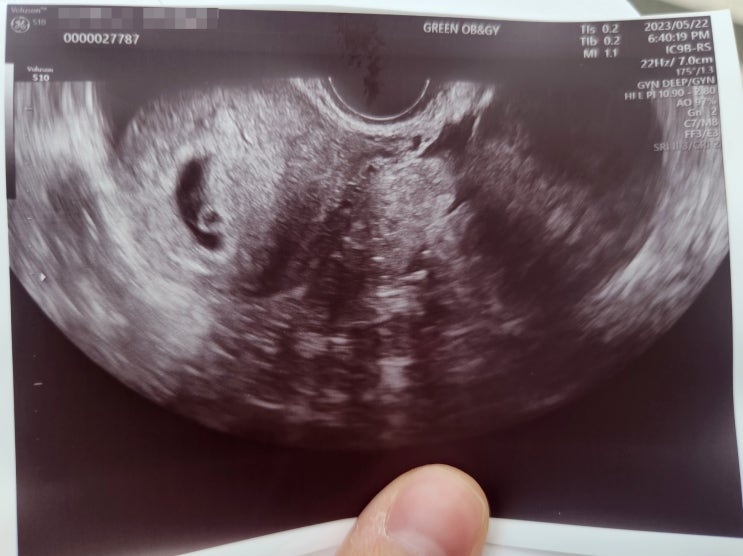

“금조, 비키니로 드러난 변화…‘뱃살 아닌 아기’ 솔직 고백에 시선 집중”

나인뮤지스 금조의 근황이 다시 화제를 모으고 있다. 최근 자신의 SNS를 통해 공개한 비키니 사진이 온라인을…